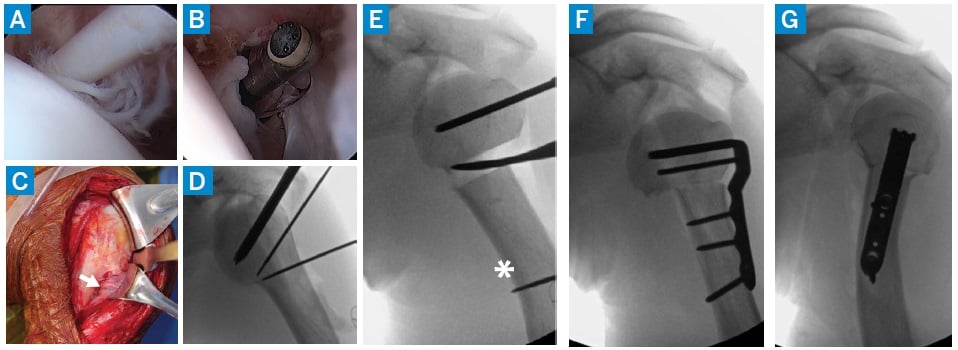

Figure 3: Intraoperative arthroscopy revealed marked long head biceps tendon degeneration at the proximal aspect of the biceps tunnel (a). Biceps tenotomy (b) and an extensile deltopectoral approach to the proximal humerus (c) were performed; the axillary nerve on the undersurface of the deltoid (arrow) was encased in subdeltoid bursal scar tissue. The biceps tendon was then mobilized from the biceps tunnel and tenodesis was performed to the conjoint tendon with nonabsorbable sutures. Guidewires were placed and the proximal fixation chisel for the 90° blade plate (d), closing wedge osteotomy (to assist with rotation deformity correction, an additional guidewire was placed distal to the osteotomy site [asterisk]) (e), and final fixation as seen on AP (f) and lateral (g) fluoroscopy.